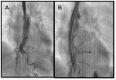

Catheter ablation of atrial ablation (AF) has become an important therapy in recent years. As with all evolving techniques, unexpected complication may occur. Atrioesophageal fistula is a very rare complication of AF catheter ablation. Described for the first time in two very experienced centers in 2004, this complication is the most dreadful and lethal among all the others related to AF catheter ablation. Its clinical presentation is extremely variable. Rapid diagnosis and surgical therapy may prevent death. This review article will summarize the risk factors, diagnosis, treatment and possible preventive strategies for this condition.